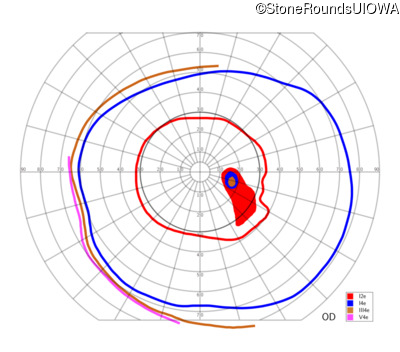

AD CSNB (IA2fii)

AD CSNB (IA2fii)